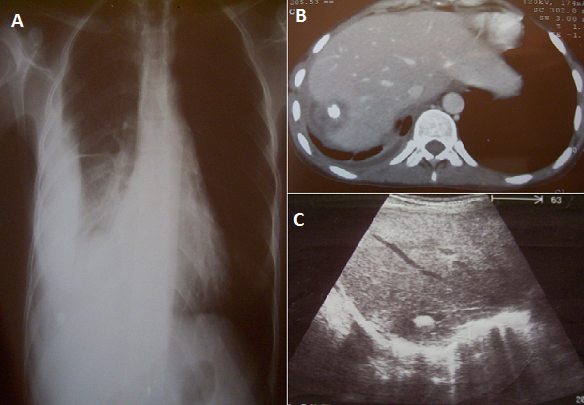

Une patiente âgée de 28ans, sans antécédent pathologique particulier, avec notion de contact avec les chiens (hébergement d'un chien au domicile), accusait depuis 2 mois des douleurs basi-thoraciques droites avec gêne respiratoire. Dix jours avant son hospitalisation, le tableau s'est aggravé par l'apparition d'une toux sèche, une asthénie et une fièvre. L'examen clinique a révélé un syndrome d'épanchement basi thoracique droit. La patiente a bénéficié d'une radiographie thoracique de face (A), qui montrait un épanchement liquidien pleural droit de moyenne abondance sans foyer parenchymateux visible. Une tomodensitométrie thoraco-abdominale a montré un épanchement liquidien pleural droit associé à une scissurite, l'épanchement communiquant par le biais d'une fistule avec une lésion arrondie, hypodense, bien limitée du dôme hépatique, renfermant une calcification périphérique et ne se rehausse pas après injection de produit de contraste (B). Le complément échographique réalisé a confirmé la présence de la lésion du dôme hépatique avec les caractères sémiologiques suscités (C). Biologiquement, on notait une discrète élévation de la VS à 15mm la première heure avec une sérologie hydatique positive. La patiente a bénéficié d'une chirurgie avec drainage de liquide pleural et fermeture de la fistule. L'évolution post opératoire était favorable. Le kyste hydatique est une parasitose due au développement de la forme larvaire d'échinococcus granulosus. L'hôte habituel est le chien, l'homme étant l'hôte intermédiaire. Toutes les localisations sont possibles. La fistulisation dans le thorax est beaucoup plus rare et varie de 2 à 5% selon les séries.